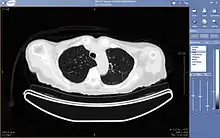

A chest image displayed via a PACS

A full PACS should provide a single point of access for images and their associated data. That is, it should support all digital modalities, in all departments, throughout the organisation.